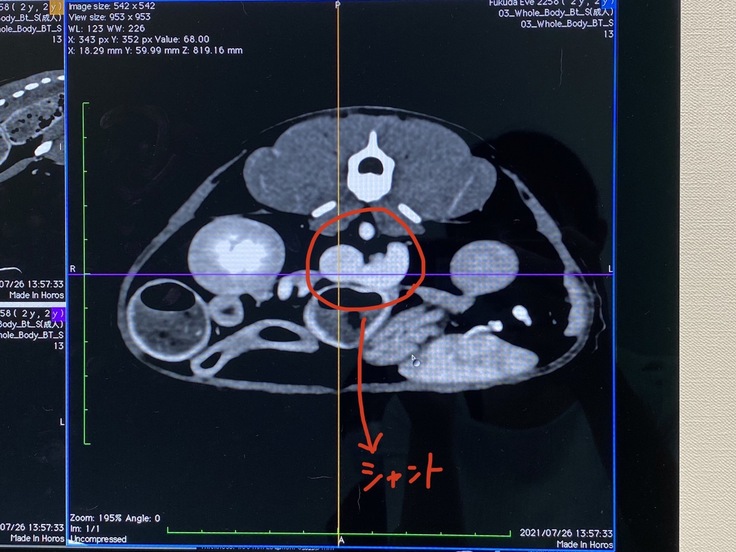

7月26日 CT検査。

門脈シャント確定。シャントが太いため

手術は二回以上は必要と診断される。

門脈シャントとは本来肝臓で解毒されるはずのアンモニア等の毒素が門脈と全身の静脈をつなぐ余分な血管(シャント)によって全身に巡ってしまう疾患です。

門脈シャントは何らかの原因で門脈が枝分かれしてしまっている場合、毒素を持ったままの血液が本来通るべき肝臓を通らずに体循環と合流してしまう事で毒素が全身を巡り様々な症状を引き起こします。

いぶの場合、開腹手術でシャント部分を結紮する方法だそうです。(シャント血管を縛る方法)

この治療法は主に肝外性シャント(本来不要である血管「シャント」が肝臓の外にあるタイプ)の場合に用いられ、シャントの部位や太さによってはは完全結紮が難しく複数回に渡って手術を要する場合があります。いぶの場合は、シャントが太いため一回で完全に結紮してしまうと、正常な血管に圧力がかかりすぎて多発性のシャント(不要な血管が増えてしまう)が出来てしまう可能性があるため少しずつ血管をしめていく事が必要だそうです。